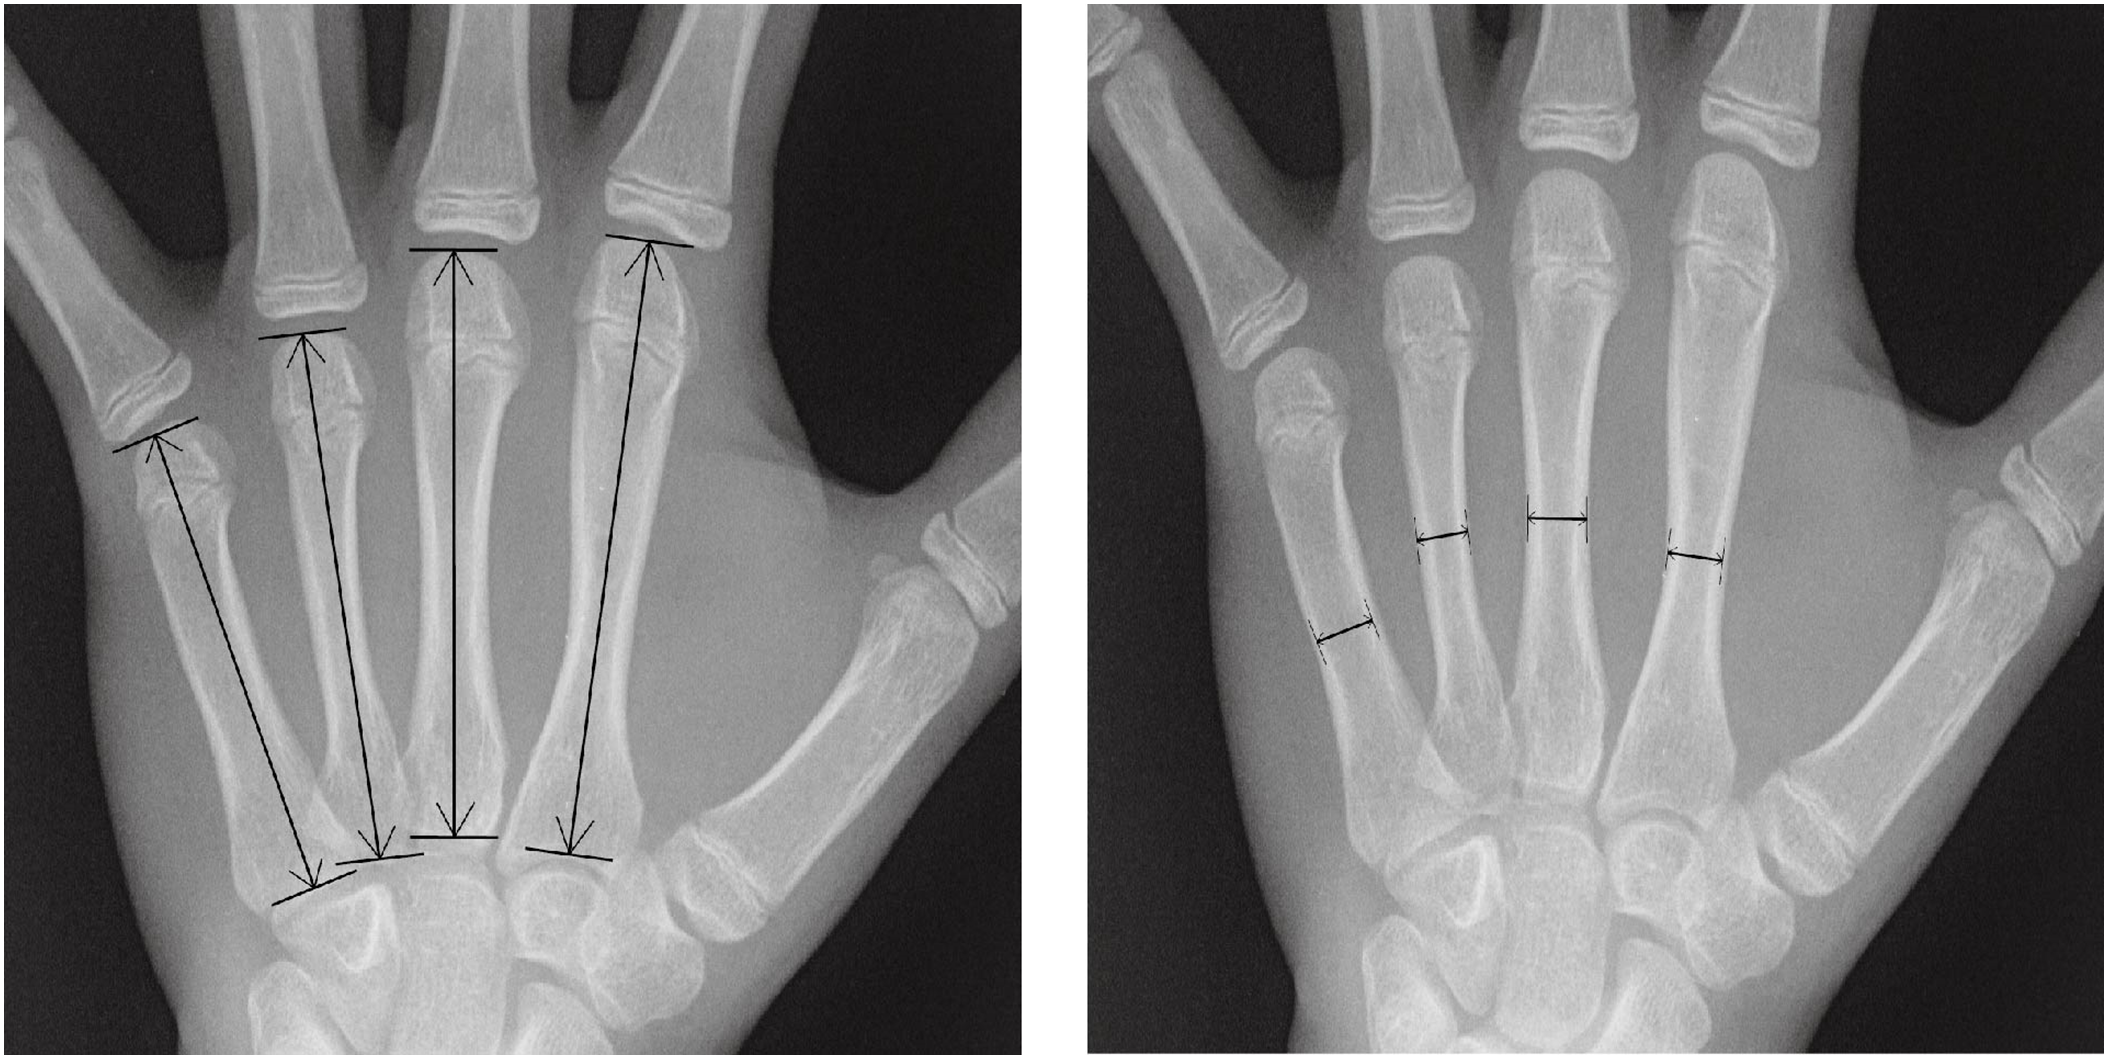

3.4 Quantitative Features Measured from Radiograph

In this study, the width and length dimensions of the 2nd–5th metacarpal bones are selected as the quantitative features. By integrating quantitative information, the model performs better in automated BAA tasks across individuals from different racial groups. To measure the dimensions in the X-ray images of the left hand bones, Adobe Photoshop CS5 is used as the image processing tool. All radiographs are captured at a resolution of 1024 dpi (dots per inch), and all the measurements are conducted in centimeters. The measurement scale is dynamically adjusted based on the image resolution, with 250 pixels representing 25 mm. Additionally, the ruler tool is employed to measure the length and width of the metacarpal bones. Length measurements are recorded based on the values displayed after using the ruler tool to draw a line. When measuring the width of bones and joints, the zoom level is set to 400% to facilitate precise observation and measurement of details. In contrast, the zoom level is set to 100% to measure the length of bones, ensuring that the entire length is visible within the field of view. By varying the zoom level, more accurate measurements at different scales are achieved, minimizing errors associated with image resolution and enhancing the overall accuracy and reliability of the measurements.

The methodology for measuring the metacarpals is illustrated in Fig. 4. A line is drawn parallel to the long axis of the diaphysis, and the length indicated by this line is defined as the bone length. Each bone’s width is measured at its thinnest part. Consequently, a total of eight features are extracted from each sample.

Figure 4: Quantitative feature measurements of the width and length in the metacarpal